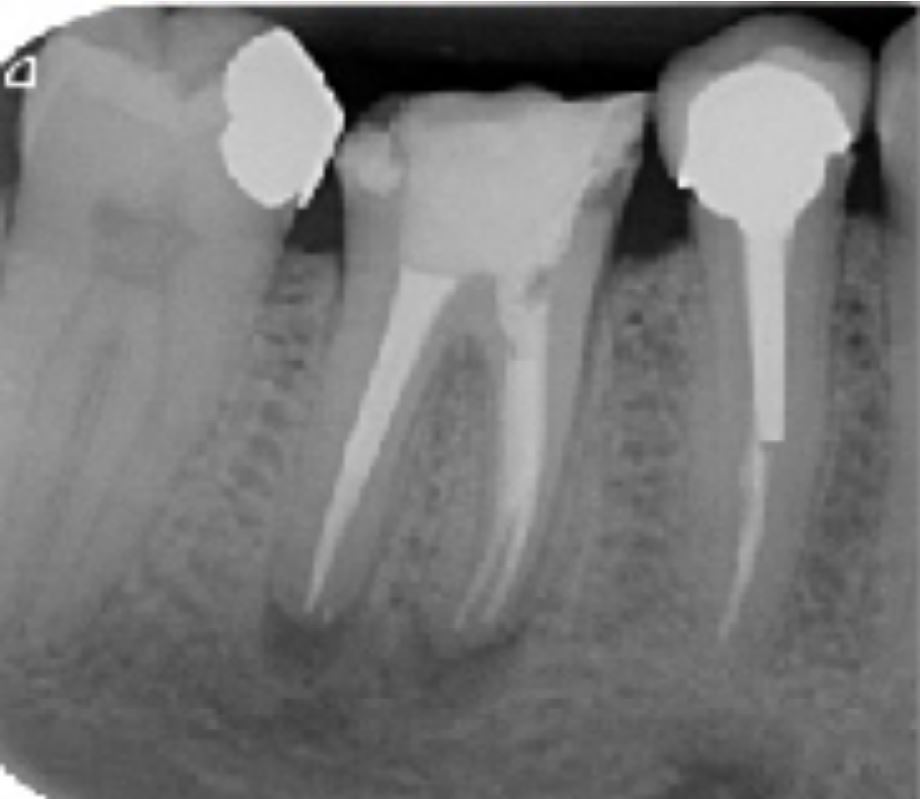

Radio post-opératoire

Alésage du système canalaire à l'aide de la séquence FANTA BLUE S4 Rotary jusqu'à la lime 35/04

Lime apical maitresse de 35/100ème

Obturation Gutta et Ciment Zinc Eugénol

Thermocompactage avec canal accessoire dans le canal distal